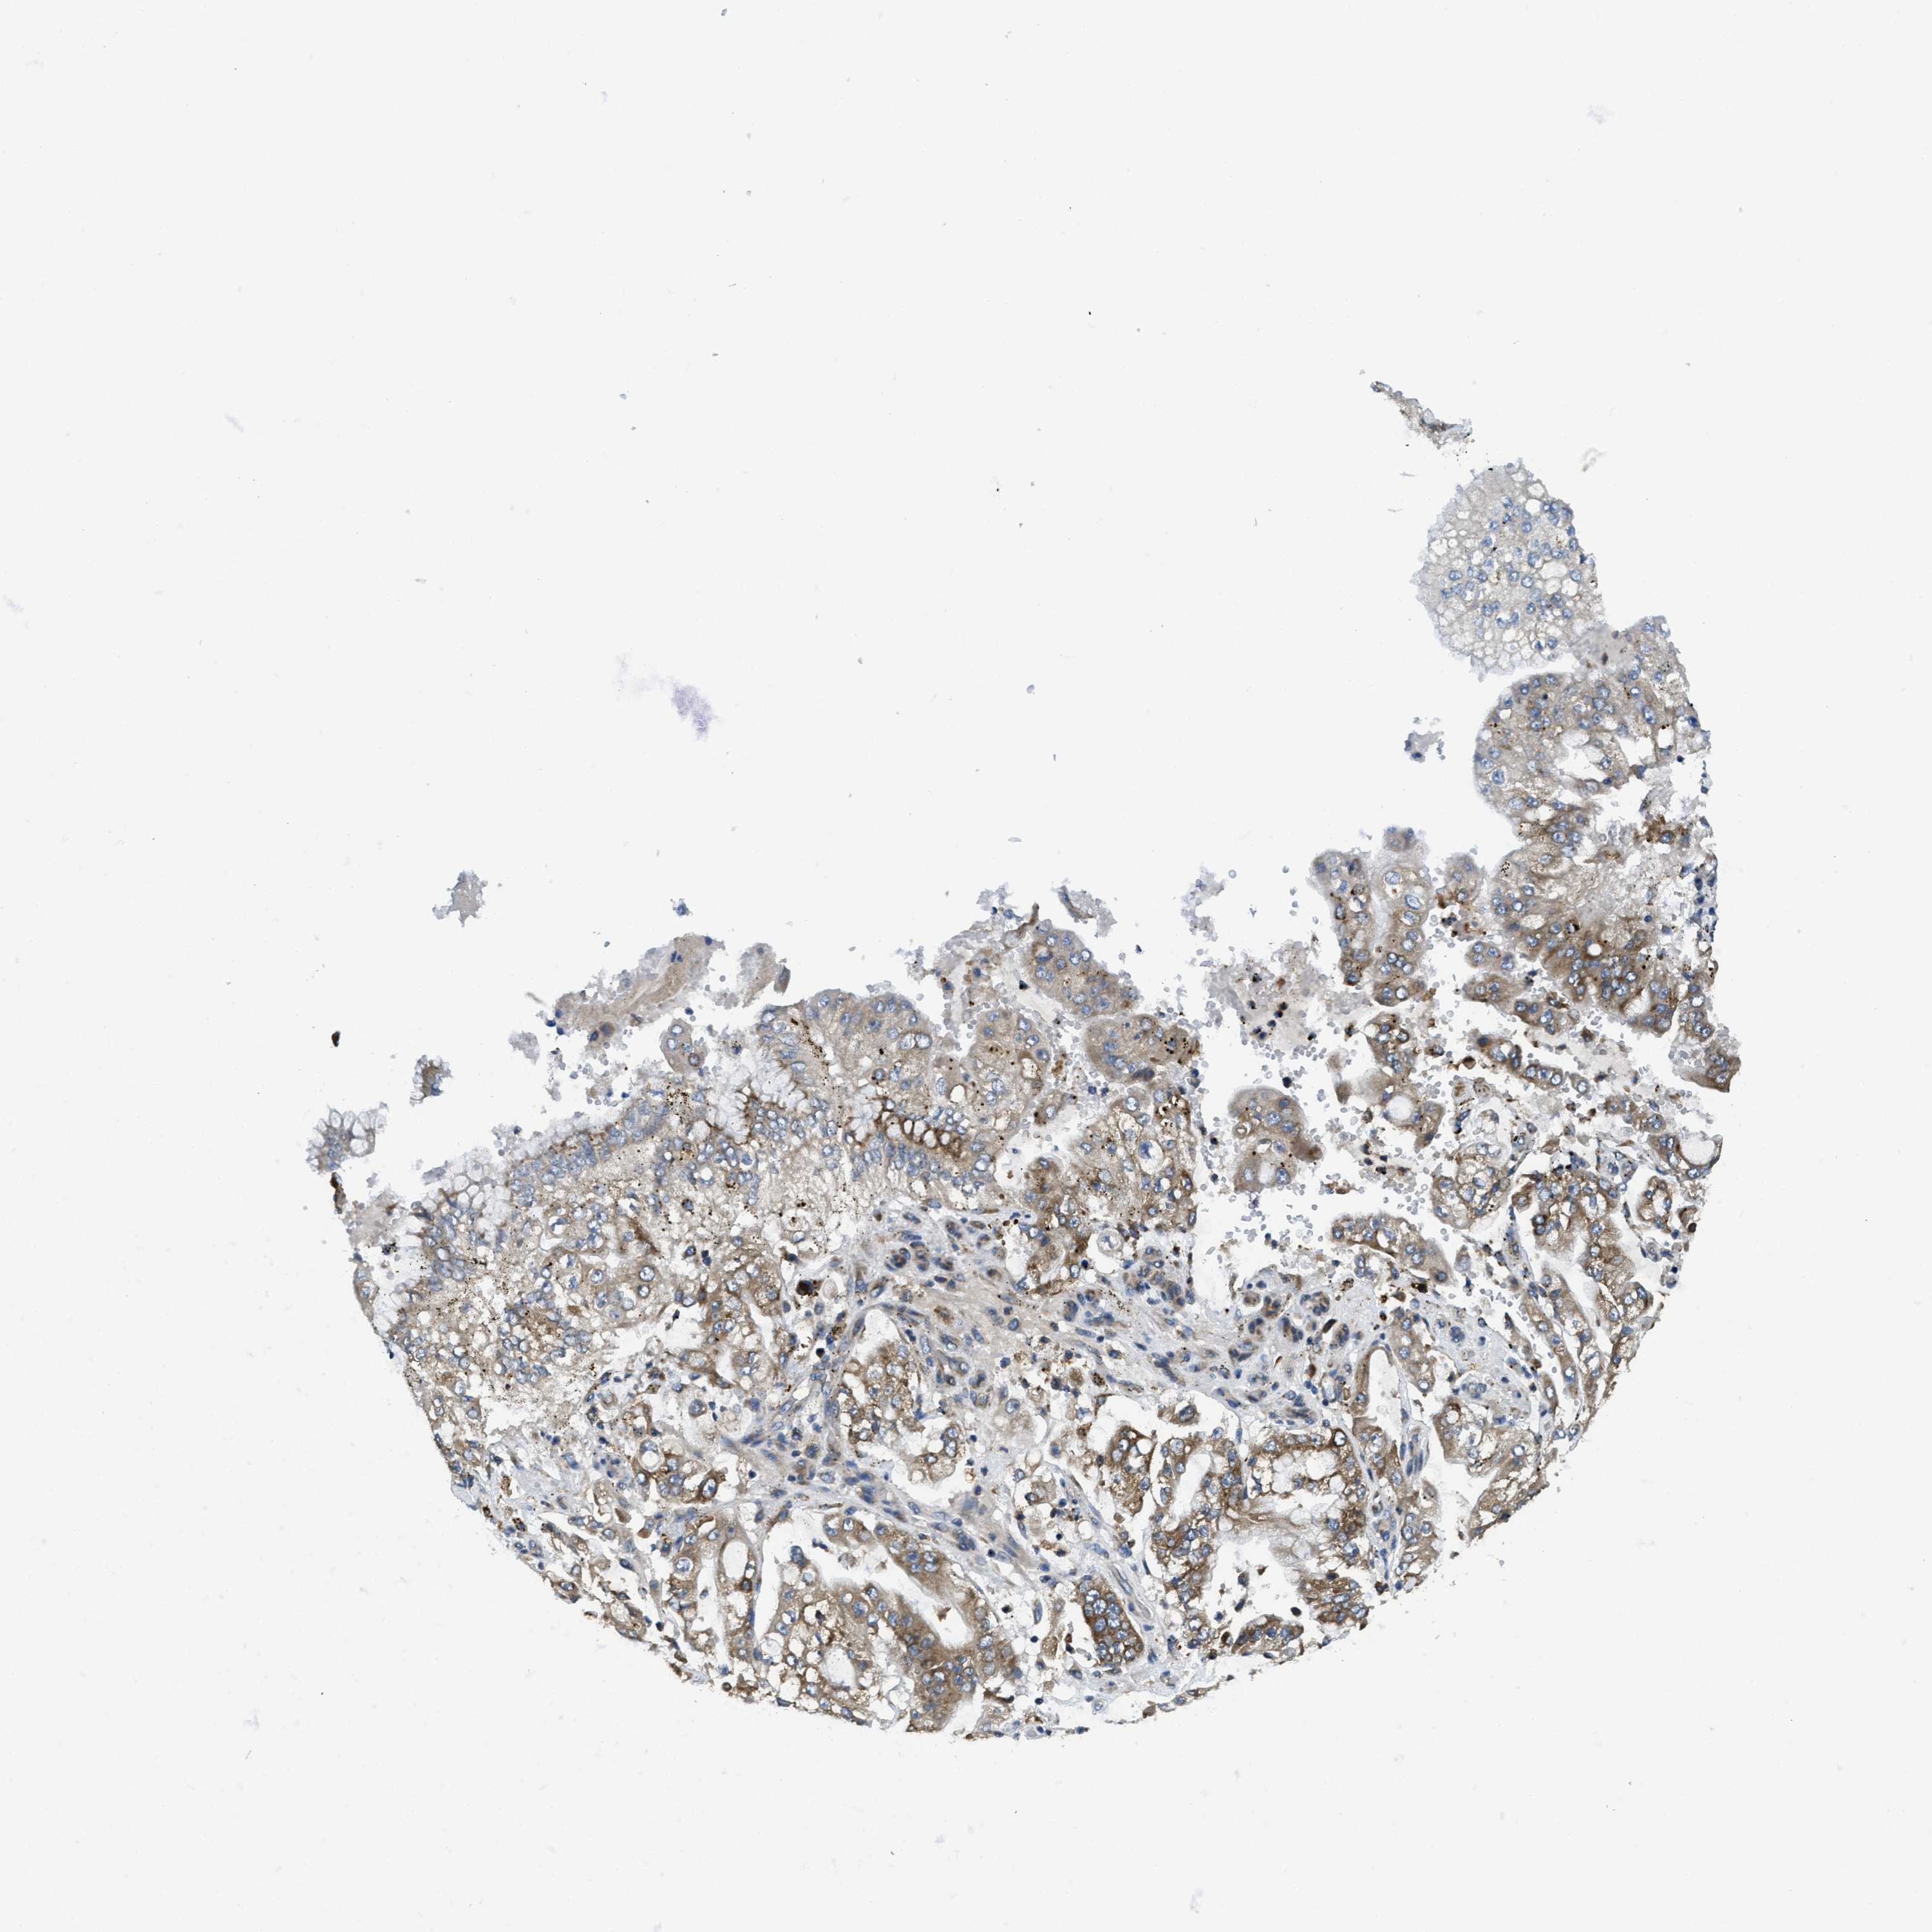

STOMACH CANCER - Protein expressioni

A mouse-over function shows sample information and annotation data. Click on an image to view it in a full screen mode. Samples can be filtered based on level of antibody staining by selecting one or several of the following categories: high, medium, low and not detected. The assay and annotation is described here.

Note that samples used for immunohistochemistry by the Human Protein Atlas do not correspond to samples in the TCGA dataset.

Antibody stainingi

Antibody staining in the annotated cell types in the current human tissue is reported as not detected, low, medium, or high, based on conventional immunohistochemistry profiling in selected tissues. This score is based on the combination of the staining intensity and fraction of stained cells.

Each image is clickable and will lead to virtual microscopy that enables deeper exploration of all samples and also displays staining intensity scores, fraction scores and subcellular localization as well as patient and tissue information for each sample.

Antibody HPA011276

Antibody HPA017062

Staining

High

Medium

Low

Not detected

Intensity

Strong

Moderate

Weak

Negative

Quantity

>75%

75%-25%

<25%

None

Location

Nuclear

Cytoplasmic/membranous

Cytoplasmic/membranous,nuclear

Adenocarcinoma, NOS

Adenocarcinoma, High grade